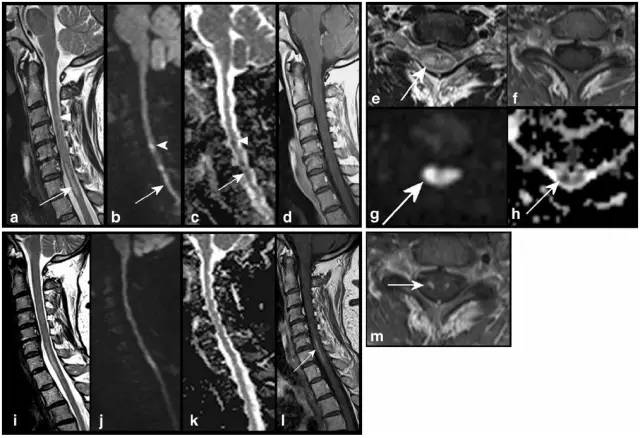

病例2:46岁女性,脊髓前动脉梗死和抗磷脂抗体综合征。发病第二天MRI(图a-h)显示T2(图a,e)不均匀高信号,病变起自C3/4(图a,箭头),一直到C7/Th1水平(图a,e箭头),DWI高信号(图b,g),ADC低信号(图c,h箭头),无强化(图d,f)。第九天随访MRI(图i-m),T2(图i),DWI(图j),ADC(图k),强化(图l),特别是前外侧强化(图m,箭头提示强化后蛇眼征)